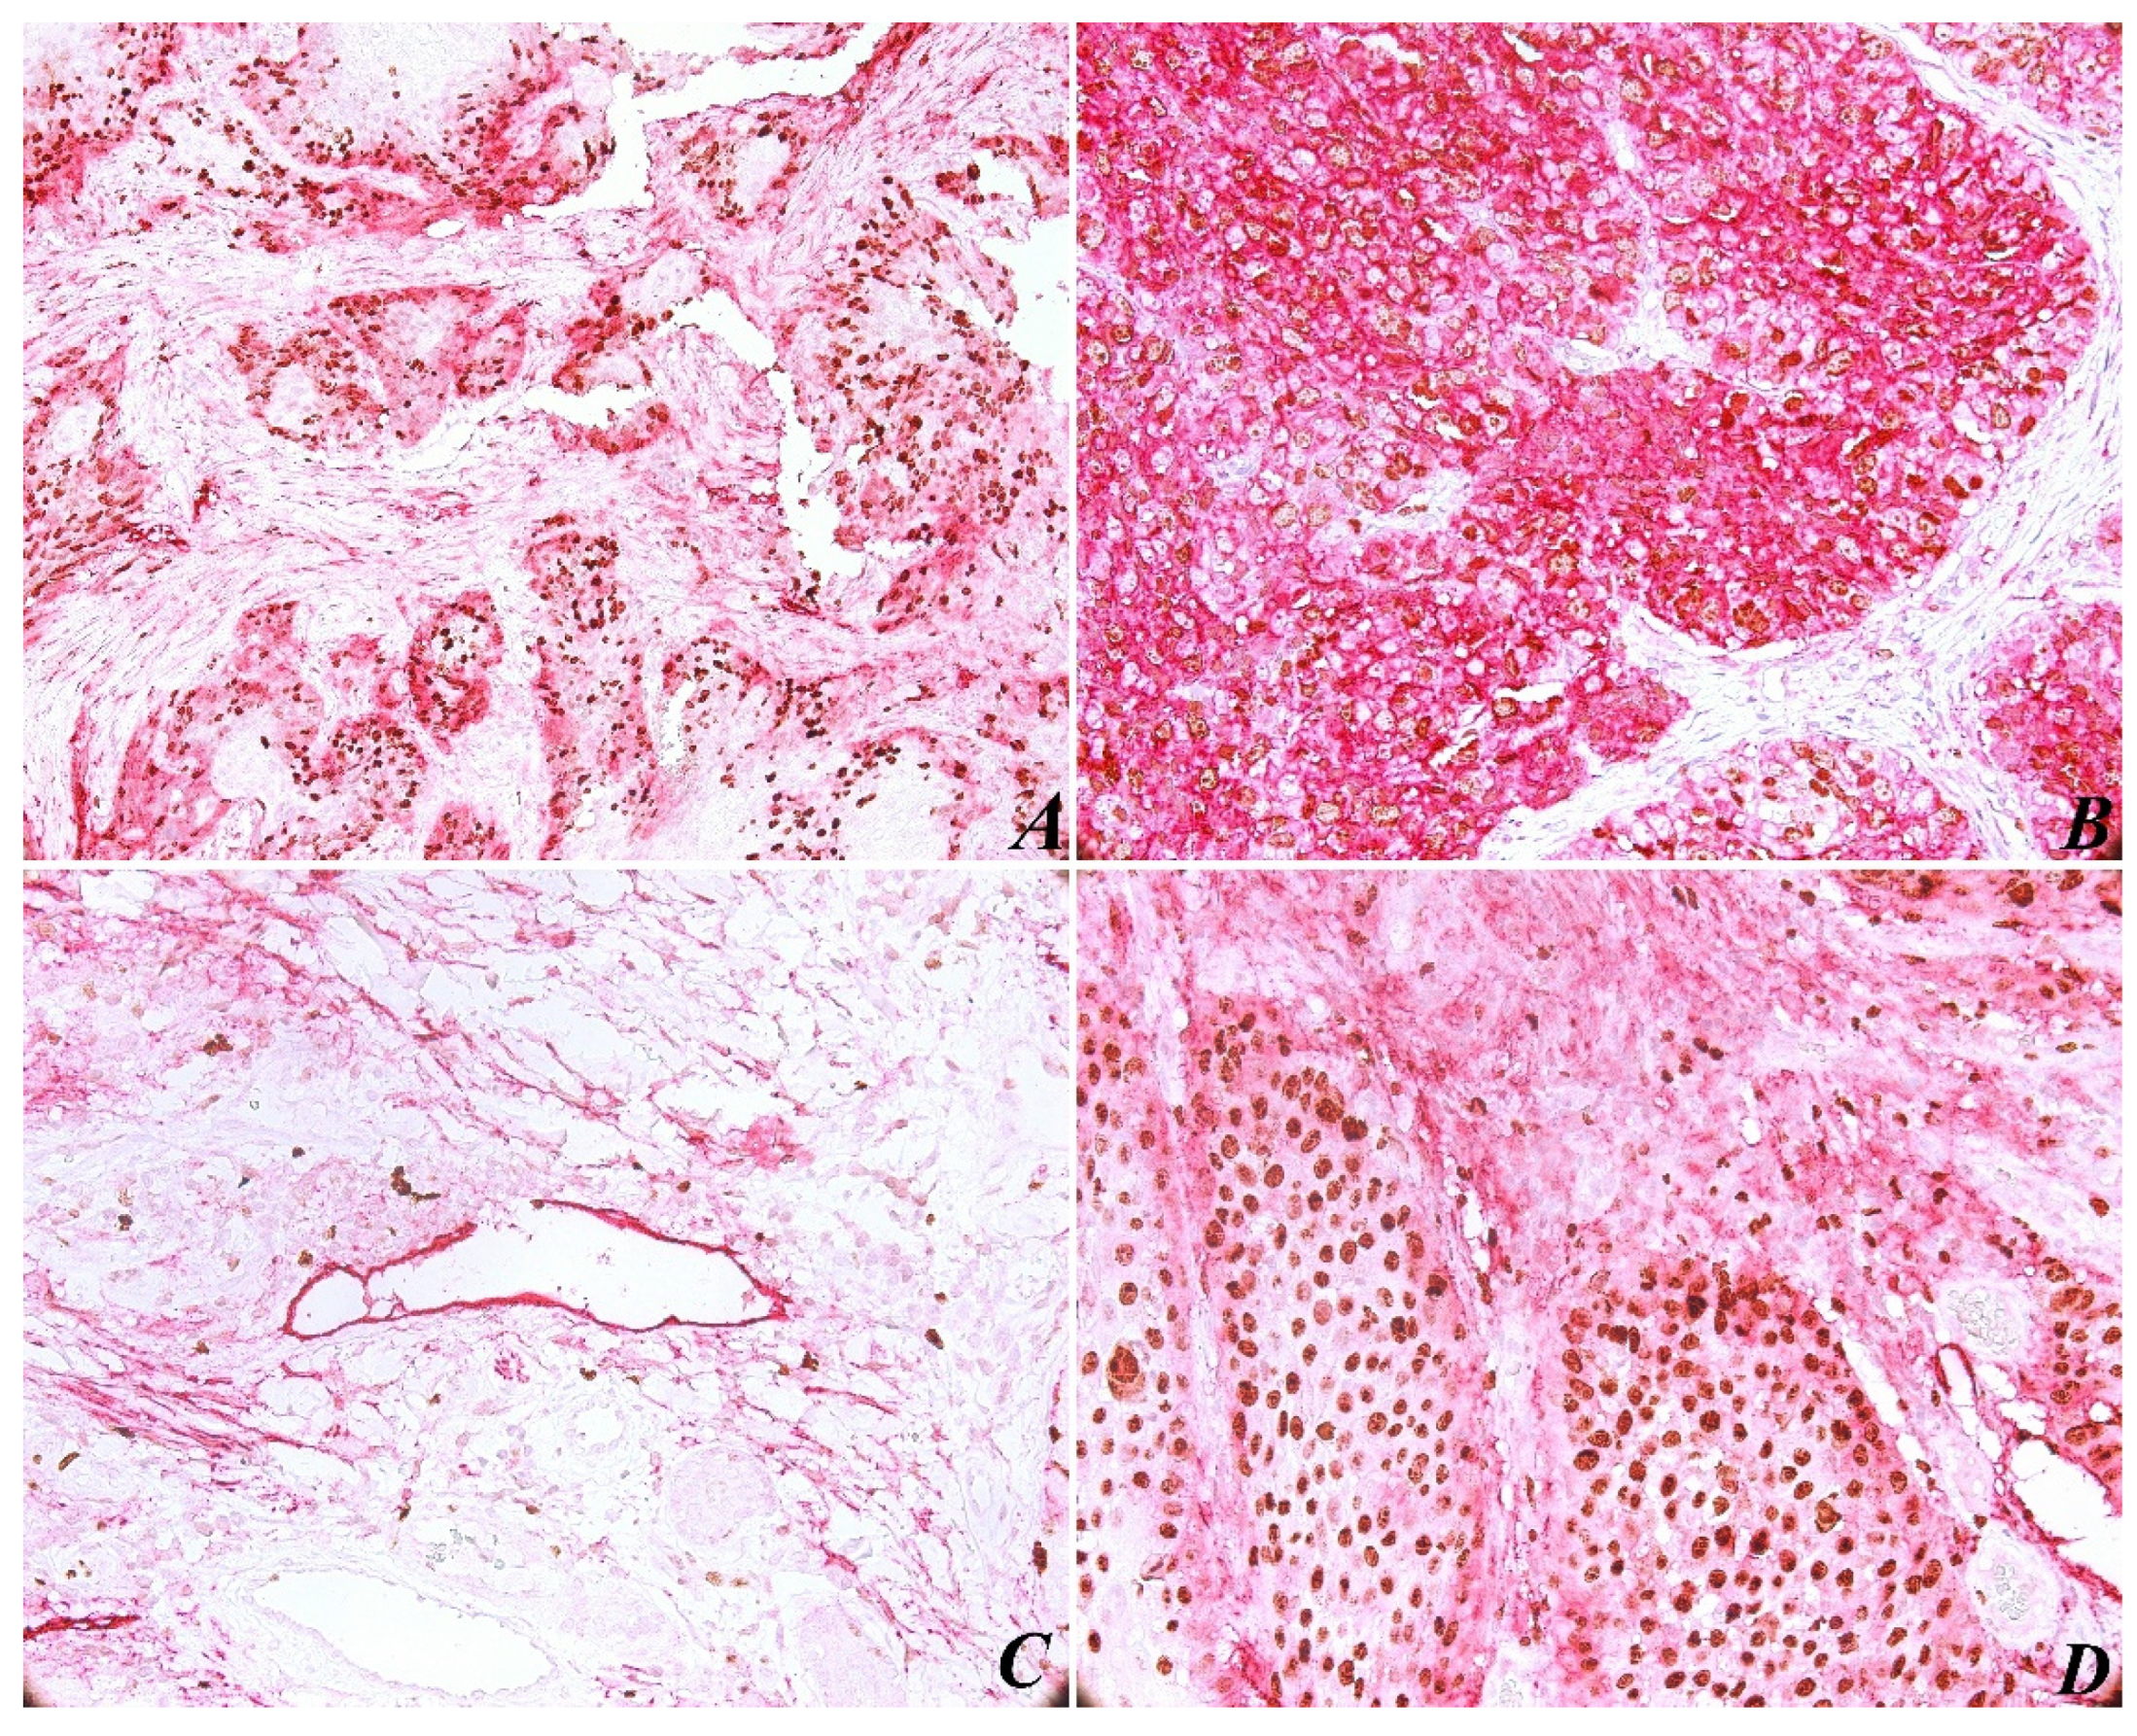

The immunohistochemical evaluation of PDPN expression was identified in almost all cases (with the exception of one case). In most tumors (85%), PDPN was identified in the basal-suprabasal layer of squamous epithelia, with both a cytoplasmic and membranous pattern. As for PDPN immunoexpressing in tumors, high reactivity was present at the periphery of most tumor areas (Figure 1A). As expected, PDPN was highly expressed in cytoplasmic areas of tumor cells (Figure 1B), correlating with high histological grading. The results show a significant correlation between PDPN immunoexpressing and histopathological grading (p < 0.05; p = 0.037) (Table 1).

Another observation concerned lymphovascular invasion (LVI), which is defined by the identification in the LV lumen of isolated tumor cells, small groups of tumor cells, or by discontinuous wall of the lymphatic vessels by tumor invasion (Figure 1C). In this case, due to Ki-67/PDPN double staining, we found 15 tissue samples with LVI, counting the entire tumor tissue sample. We found no major differences between peritumoral and intratumoral LVD, no significant correlation between LVI and histological grading (p < 0.05; p = 0.976), and tumor proliferation assessed by Ki-67 expression was not relevant (p < 0.05; p = 0.413). We believe that such a correlation was not possible because the current stage of the tumor evidence did not show loco-regional lymph node metastasis.

The immunohistochemical evaluation of Ki-67 nuclear staining was observed in all 50 cases. An increased Ki-67 proliferation index was present in 82% of tumor areas (Table 4), and a statistical correlation was found between this and histological grading (p < 0.05; p = 0.050). In addition, we recorded a statistically significant correlation between Ki-67 expression and PDPN expression (p < 0.05; p = 0.028). However, an analysis of Ki-67 nuclear labeling and LMVD profile was not significant (p < 0.05; p = 0.896). In the tumor areas, both peripheral and central cells of the tumor islets were positively immunostained with Ki-67 (Figure 1D). Immunoreactivity for Ki-67 was limited to the nucleus in all samples, and PDPN staining was present in different intensities in cytoplasmic tumor cells.

Figure 1. Head and neck squamous cell carcinoma specimens stained with the double immunostaining Ki-67 and podoplanin (purple for podoplanin and brownish for Ki67). High reactivity of podoplanin was present at the periphery of tumor areas, score +2, original magnification ×200 (A). Height expression of podoplanin score +3 and Ki-67 score +3 in tumor area, original magnification ×200 (B). Peritumoral lymphatic vessel with endothelial wall disrupted by tumor cell invasion, original magnification ×200 (C). Podoplanin expression at the periphery of tumor and proliferation index Ki-67 score +3, original magnification ×400 (D).